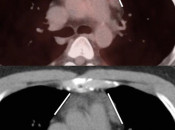

- Beam Hardening

- Diaphragmatic Mismatch

- Linear Hand Motion

- Attenuation Correction